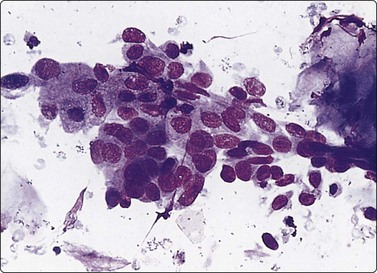

image image

Fig. 7.15 Regenerative epithelial atypia in mastitis

(A) Atypical, reactive/regenerating epithelial cells with a background of histiocytes, inflammatory cells and debris (MGG, HP); (B) Corresponding tissue section (H&E, IP).